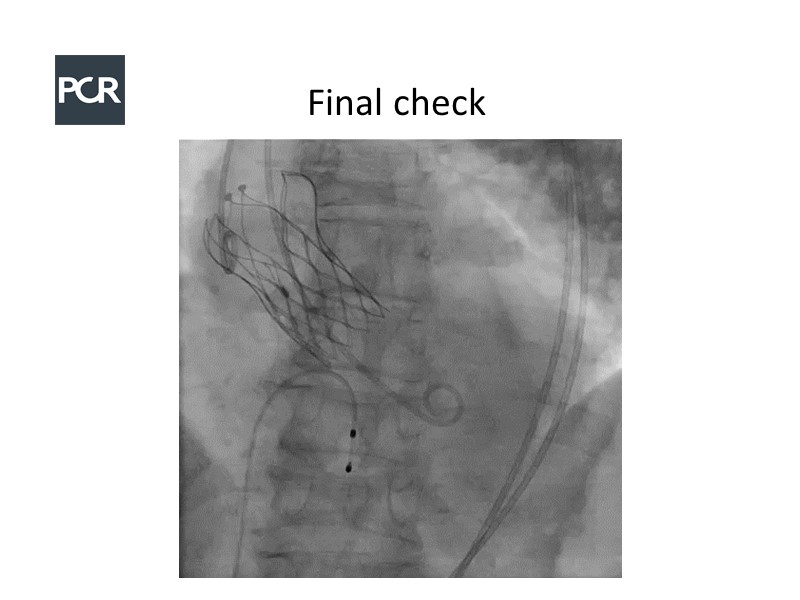

In this session, a panel of experts introduce the VitaFlow TAVI system, a good option for patients with complex anatomies. They also present the five-year results of VitaFlow in severe aortic stenosis.